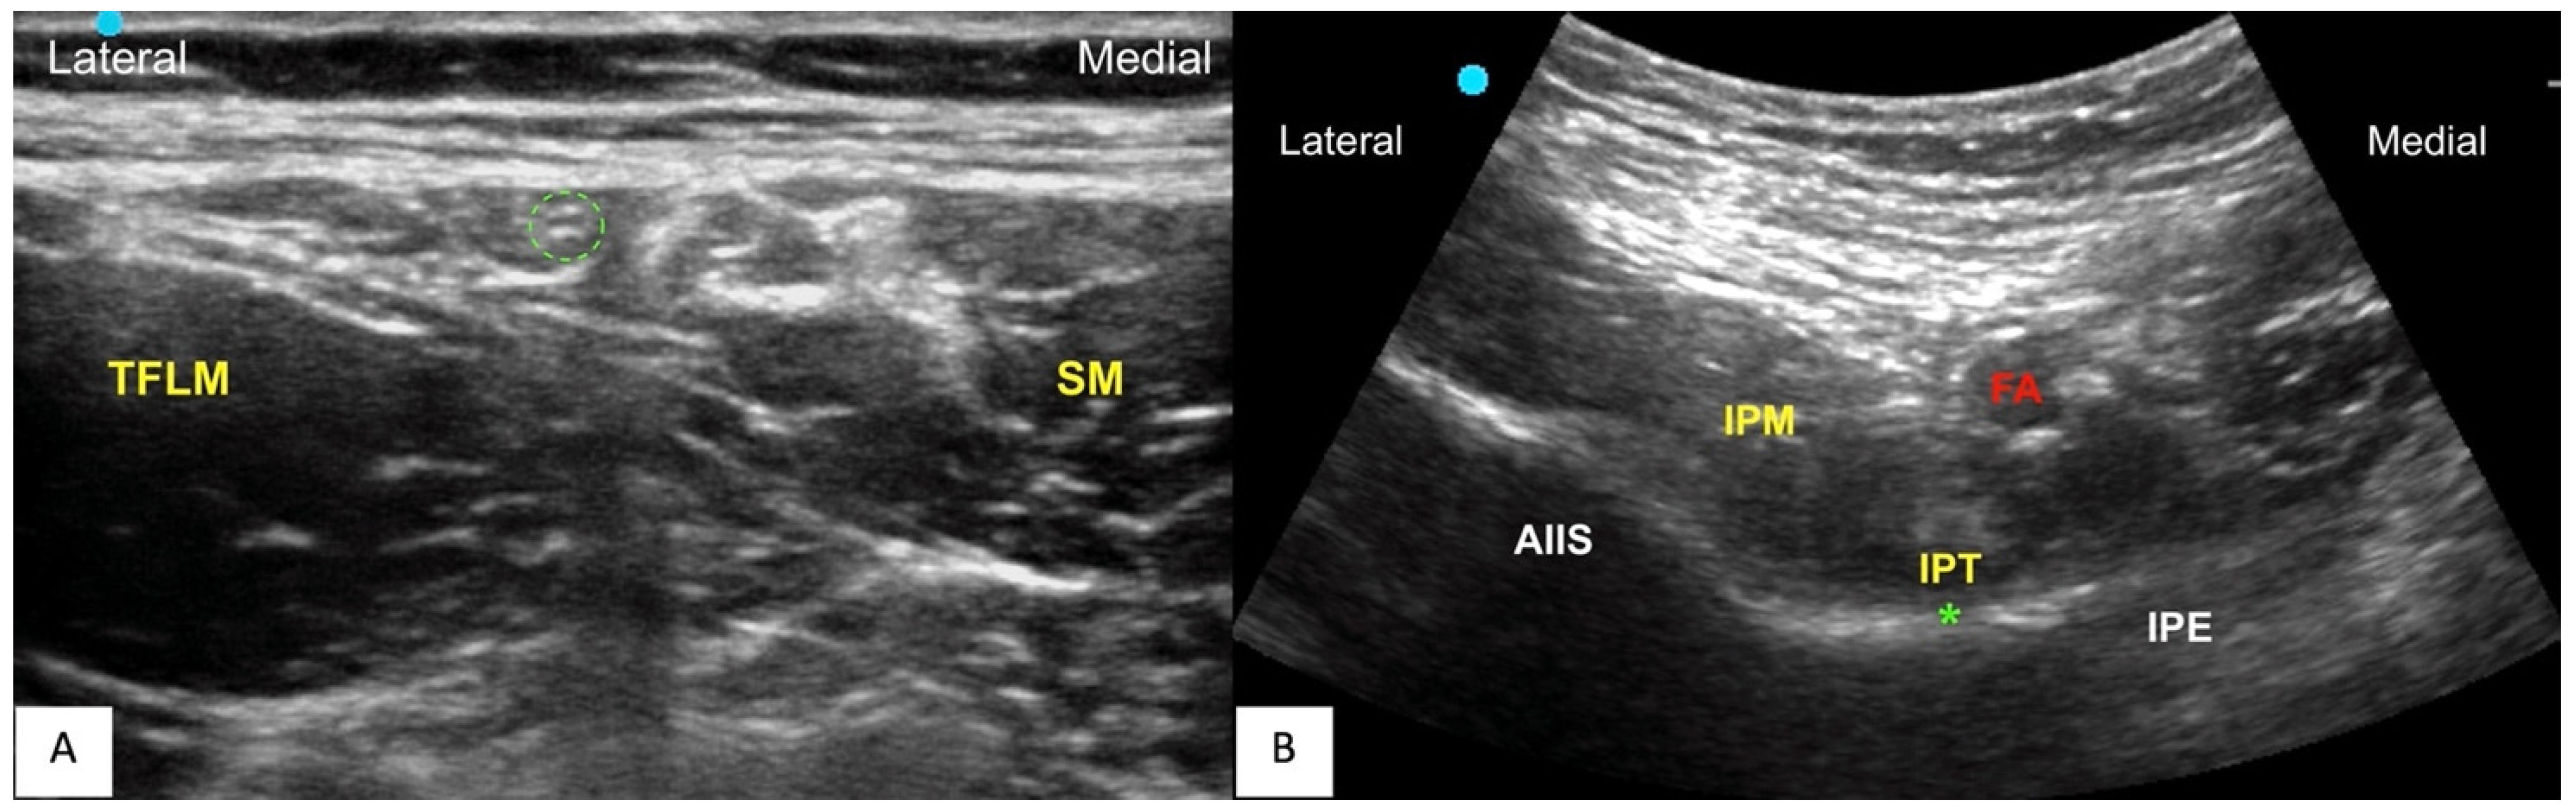

2.2. Interventions